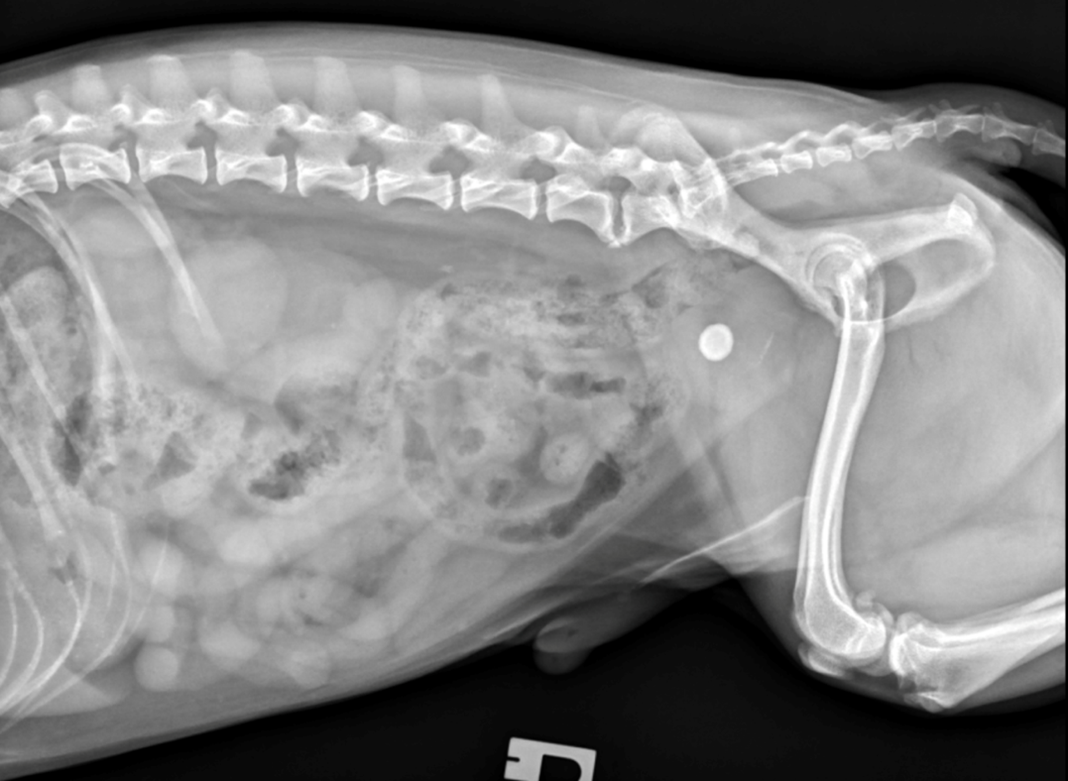

3) Urolithiasis

A five-year-old neutered male Shih Tzu presented with a one-month history of haematuria, non-responsive to non-steroidal anti-inflammatory and antibiotic therapy. Physical and external urogenital examinations were unremarkable.

Haematology, biochemistry and urinalysis were unremarkable. However, abdominal radiography revealed a moderately sized, round, smoothly marginated mineral opacity in the urinary bladder on abdominal radiography, consistent with a cystolith (Figure 4). This was removed via minimally invasive cystotomy, and analysis confirmed this to be calcium oxalate.